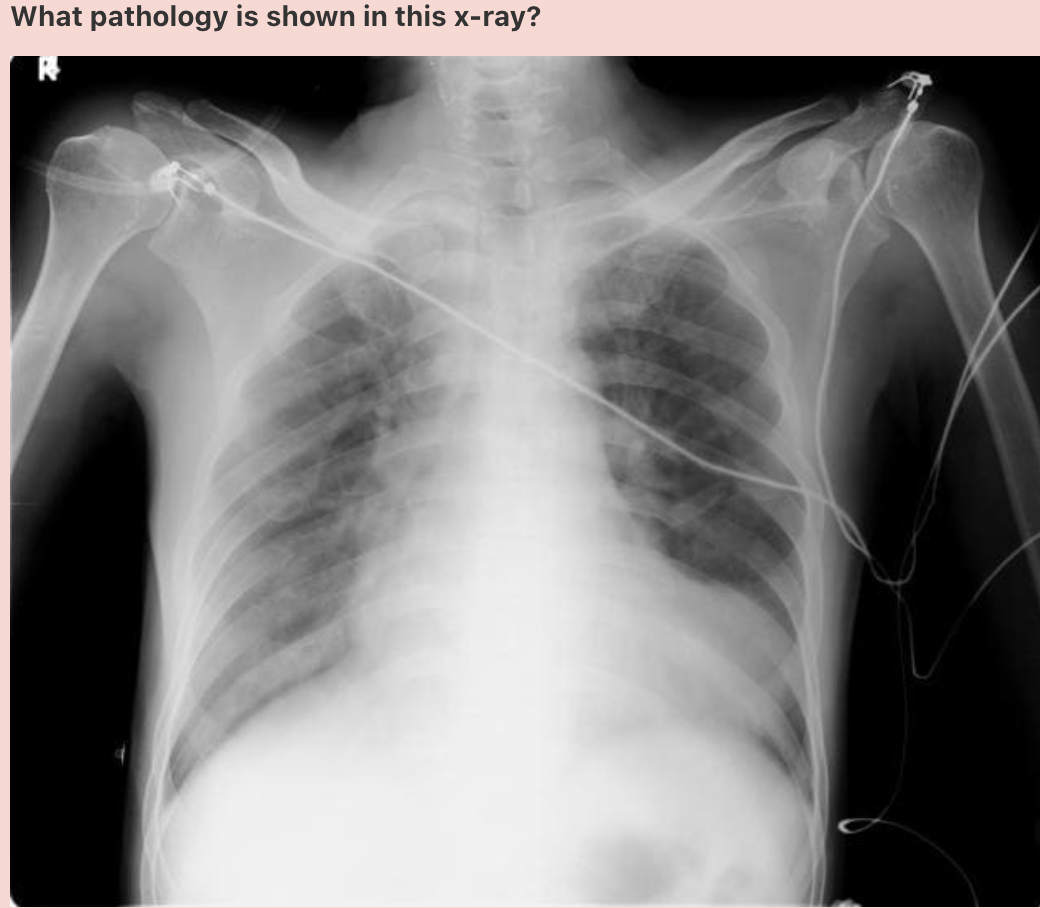

Answer: Left ventricular aneurysm

Portable chest radiograph taken in ICU reveals a bulge at the cardiac apex.